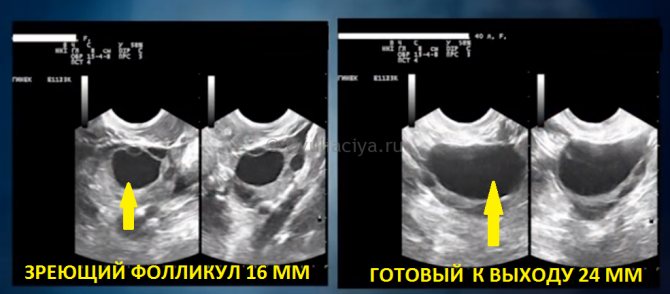

Начиная с восьмого и по десятый день явно выделяется доминантная клетка, размер которой доходит до 14 мм, а в течение суток увеличивается еще на 3 мм. При этом остальные фолликулы постепенно уменьшаются, а затем и вовсе исчезают.

За пару суток до выхода яйцеклетки эта клетка достигает 20-22 мм. В данном случае все зависит от менструации. А уже спустя две недели наступает овуляция и пузырек лопается.

На 7-8 сутки менструального цикла появляется доминантный фолликул, габариты которого не превышают 9-11 мм. С каждым днем капсула увеличивается на 1-2 мм и уже к периоду овуляции она составляет 18-24 мм в диаметре. Это предельный максимум, что говорит в пользу его скорого разрыва и овуляции.

- На 11–14 день он достигает 20–25 мм, и готов к выходу.

Когда наступает долгожданная овуляция, размер фолликула в диаметре – 20–25 мм. При нормальном развитии в это время происходит разрыв фолликула и выход женской клетки. p, blockquote 10,0,0,0,0 —>